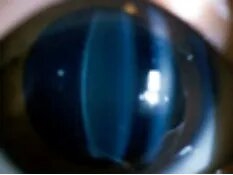

正常眼

白内障

白内障,顾名思义,就是原本透明的晶状体变得浑浊,导致光线无法正常穿透,成像在视网膜上的画面自然变得模糊、昏暗。就像相机镜头蒙上了一层厚厚的水垢,再美的风景也无法清晰呈现。医学上对白内障的定义是:晶状体蛋白质变性导致的混浊,阻碍光线投射到视网膜上,引起视力下降、视物模糊等症状。

这里的关键是“蛋白质变性”—— 晶状体的主要成分是蛋白质,占比约 60%-70%,这些蛋白质以特定的结构有序排列,才能保证晶状体的透明性。当某些因素导致这些蛋白质的结构被破坏,原本有序的排列变得混乱,就会形成不透明的混浊物,如同透明的蛋清煮熟后变成白色的蛋白,再也无法恢复透明,光线无法透过。